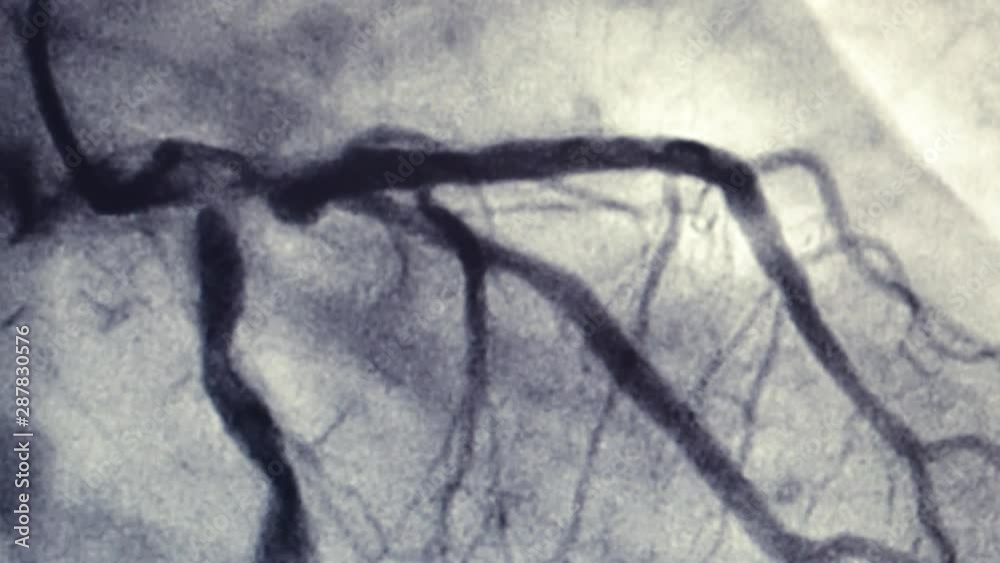

A. Left heart catheters in common use for selective coronary Catheters Used For Left Ventriculography Catheterization of the left side of the heart is done to obtain information about the heart chambers on the left side (left atrium and left ventricle), the. Correlation of the findings from coronary angiography with those from left ventriculography permits identification of potentially viable areas of the myocardium that. This widely used method requires separate preformed catheters for the right. Catheters Used For Left Ventriculography.